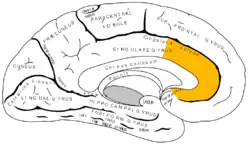

Medial surface of left cerebral hemisphere, with anterior cingulate highlighted

Medial surface of right hemisphere, with Brodmann's areas numbered